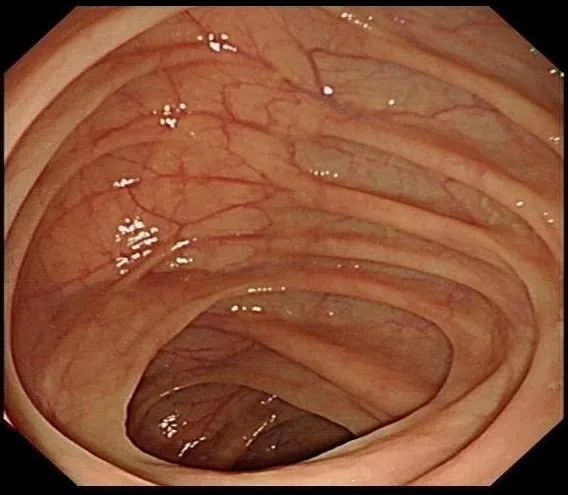

文中提到作者的肠子变黑了 , 用医学术语讲 , 应该是“结肠黑变”或“结肠色素沉着” , 就像肠粘膜上长了“老年斑” 。 肠镜下 , 正常的结肠粘膜是淡红色的 , 表面光滑平坦 , 可以见到清晰的血管纹理 。 结肠黑变的粘膜呈现深浅不等的褐色 , 甚至是黑色 , 有像豹纹、蛇皮一样的斑纹 。

正常肠粘膜、黑变的肠粘膜(密恐者谨慎左滑)丨段卓洋供图